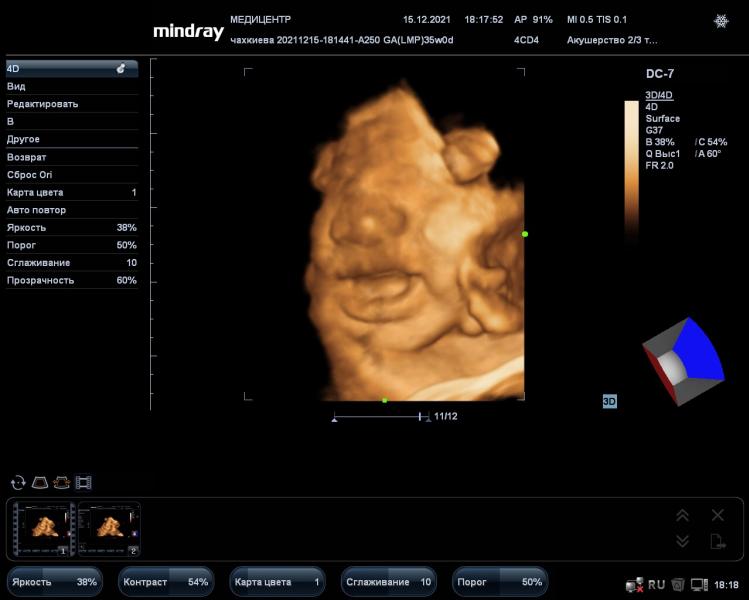

А лежал ребёночек не вниз головой?) у вас вот головка вся хорошо видна

Мне делали, но врач никак не могла нормально поймать ракурс и сделать фото, т.к. сын упирался лицом в стенку😄